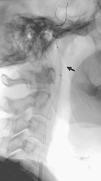

Fig. 3. --(A) Imagen de reconstrucción volumen rendering. (B) Reconstrucción mini-MIP de la arteria carótida izquierda. Estudio de angio-CT donde se observa la bifurcación carotídea y la porción proximal de ACI sin ninguna estenosis de significación.